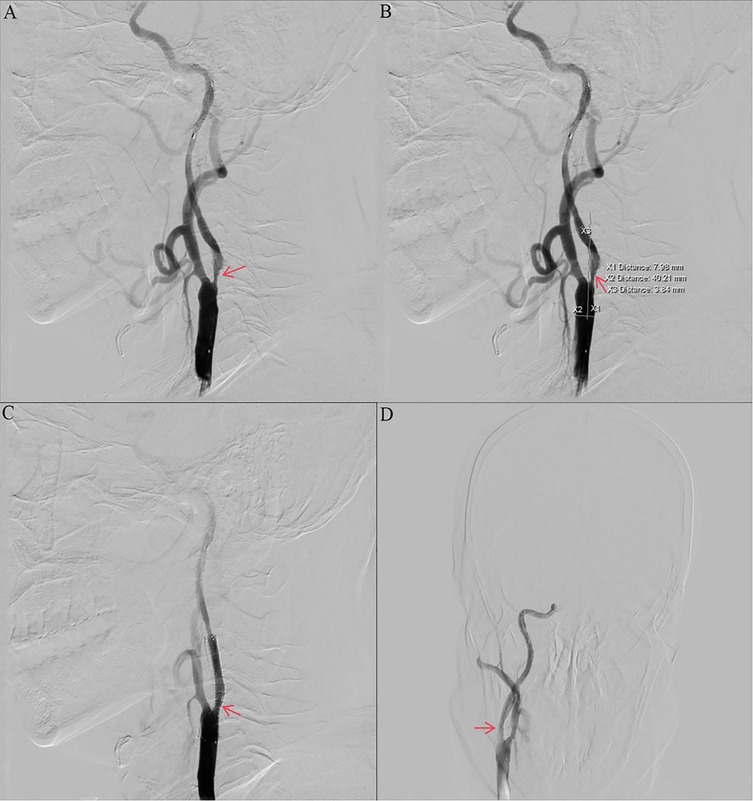

Other auxiliary investigations—including blood glucose, blood lipids, liver and renal function tests, coagulation profile, urinalysis, and thyroid antibody analysis—were unremarkable. Cardiac ultrasound and electrocardiogram findings were also normal. Vascular Surgery consultation recommended carotid endarterectomy (CEA) under general anesthesia. However, the patient and his family declined the procedure due to concerns regarding the risks associated with general anesthesia and the required neck incision. The patient decided to undergo internal carotid artery stenting under local anesthesia. Preoperative routine blood count (obtained two days prior to surgery) revealed a platelet count of 574 × 109/L. Intraoperative angiography demonstrated approximately 90% stenosis within the C1 segment of the right internal carotid artery (Figures 2A,B). The vessel diameter distal to the stenosis measured approximately 2.5 mm, while the common carotid artery diameter was approximately 7.9 mm. The stenosis was pre-dilated using a 4 mm × 30 mm LitePAC balloon inflated to 8 atmospheres(Atm). Subsequently, a 9 mm × 40 mm PROTEGE stent was successfully deployed across the stenotic segment. Post-procedural imaging showed improved antegrade flow with residual stenosis estimated at approximately 10%. Routine blood count on postoperative day 1 documented a platelet count of 415 × 109/L.

Figure 2

Preoperative and postoperative digital subtraction angiography. (a, b) Angiography of the right ICA before CAS showing stenosis with ulcers (NASCET 90% stenosis). (c, d) Angiography of the right ICA after CAS showing no residual stenosis and no thrombosis. ICA, internal carotid artery; CAS, carotid artery stenting; NASCET, North American Symptomatic Carotid Endarterectomy Trial; DSA, digital subtraction angiography.

The patient received dual antiplatelet therapy (aspirin and ticagrelor) and statin therapy. A stent was successfully implanted in his right internal carotid artery (Figures 2C,D). The CRUSADE scoring system was used to dynamically assess the risk of bleeding during hospitalization (in this case, the score was 24, which is low-risk), and hemoglobin alert values were set (immediate intervention for a drop of >2 g/dl). No recurrent cerebral infarction occurred. He was discharged on hospital day 19 with a modified Rankin Scale (mRS) score of 1. His discharge regimen included continued aspirin, ticagrelor, statin, and hydroxyurea. Discharge laboratory results showed a platelet count of 317 × 109/L (within normal range). Based on the platelet count trajectory and consultation with Hematology, the hydroxyurea dose was reduced to 500 mg/day. At the 1-month follow-up, his symptoms had significantly improved, with a platelet count of 471 × 109/L. Three-month follow-up included carotid ultrasound and platelet assessment (408 × 109/L). The ultrasound demonstrated a patent right carotid stent with smooth blood flow (velocity of 78 cm/s) and no evidence of restenosis. Following completion of 3 months of dual antiplatelet therapy (DAPT) and in accordance with ISTH Antithrombotic Guidelines for Myeloproliferative Neoplasms, ticagrelor was discontinued and antiplatelet therapy was transitioned to aspirin monotherapy. Throughout follow-up, the patient exhibited no progression to other hematologic complications associated with ET.